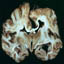

Patients with Creutzfeldt–Jakob disease (CJD) may exhibit characteristic abnormalities on the electroencephalogram (EEG). However, these abnormalities have been associated with a number of cases of drug toxicity. We report a case of CJD-like syndrome associated with gabapentin. A 78-year-old man was hospitalized for recurrent falls. Three months prior to admission, gabapentin was prescribed to treat symptoms of trigeminal neuralgia. The patient subsequently presented with a two-month history of worsening gait abnormalities, negative myoclonus, and cognitive impairment. The EEG showed diffuse background slowing with larger amplitude delta discharges, which at times appeared triphasic, raising the possibility of CJD. The gait abnormalities and myoclonus resolved and the EEG normalized after the gabapentin was discontinued. Several cases of drug-induced CJD-like syndrome have been reported, mainly presenting with cognitive impairment, myoclonus, Parkinsonism, and EEG abnormalities. This patient may have been predisposed to adverse neurological effects from gabapentin owing to age, concurrent renal insufficiency, and cardiac disease. We concluded that it is imperative to include drug toxicity in the differential diagnosis of patients presenting with clinical manifestations and EEG findings suggestive of CJD, particularly in the setting of advanced age and comorbidities.